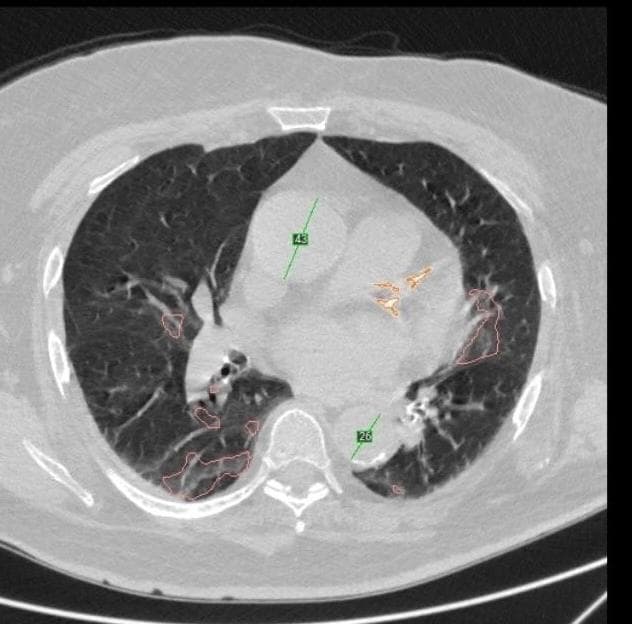

«При помощи искусственного интеллекта можно сделать анализ компьютерной томограммы органов грудной клетки и в процессе исследования получить дополнительные данные. Если рассмотреть на примере нашего пациента, то нам удалось обнаружить высокий кальциевый индекс, который говорит о поражении коронарных артерий. У пациента до этого не была выявлена ишемическая болезнь сердца, но в ходе дополнительного обследования обнаружен высокий уровень холестерина и наличие наследственного анамнеза по ишемической болезни сердца», - отметил Николай Мельников, заведующий диагностическим отделением областной больницы № 19.

Внедрение технологий искусственного интеллекта в областной больнице № 19 проходит в рамках пилотного проекта «Ретроспективный анализ данных компьютерной томографии органов грудной клетки».